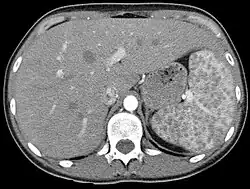

Sarkoidose der Milz in der Computertomographie: viele kleine Knötchen in der Milz rechts im Bild